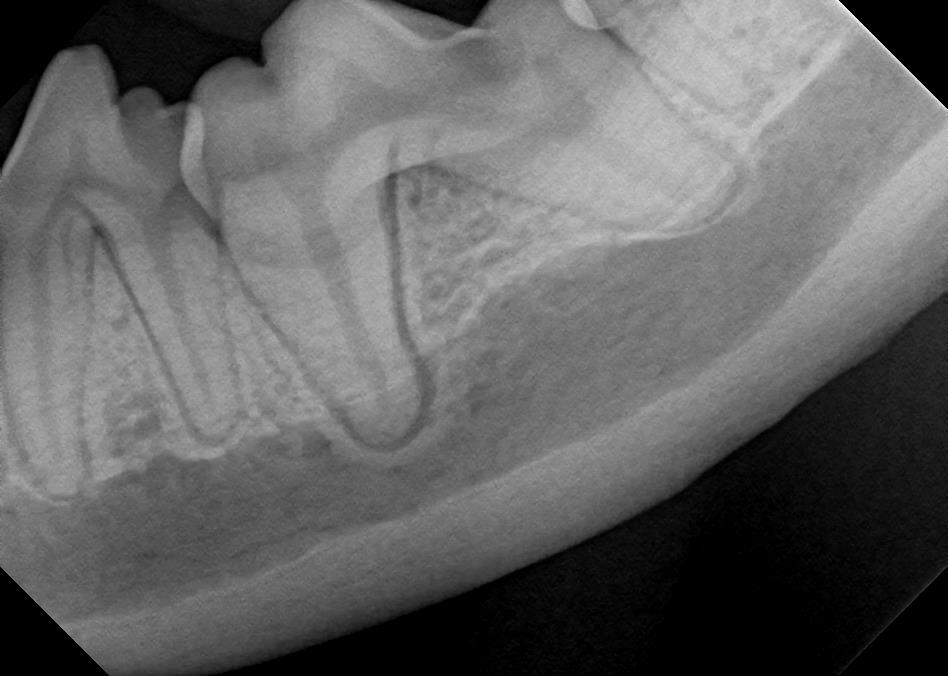

Examples of healthy teeth:

At A Couple of Vets, our animal hospital staff is well-versed in the latest dental cleaning techniques to remove plaque and tarter from the teeth’s surface as well as from below the gum line. We perform dental x-rays at every cleaning to ensure that the teeth are completely healthy. They may look good on the surface, but many problems occur below the gum line and are only visible with x-rays.